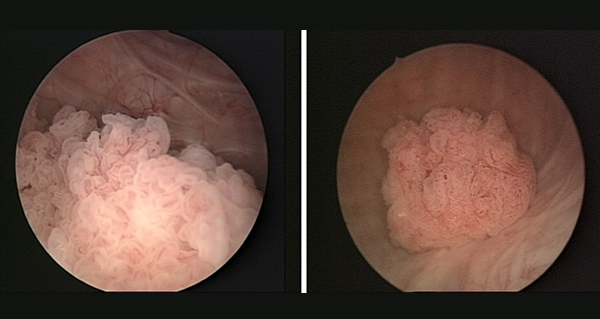

CYSTOSCOPIC VIEW OF BLADDER TUMOR

TUR OF BLADDER TUMOR